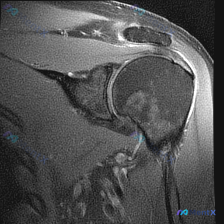

踝关节MRI看到大量软组织积液,别只想到普通滑膜炎!

刚看到一个很有讨论价值的踝关节MRI读片病例,整理了一下资料和分析思路,跟大家分享。 病例影像基础信息 这是踝关节MRI-T2序列矢状位图像,核心问题是“影像中可以看到什么?提示软组织积液”。 先给大家整理影像所见: 1. 骨性结构:胫骨远端、距骨、跟骨、舟骨等结构显示清晰,骨髓信号整体正常,未见明...

病例影像读片分享 今天整理了一例踝关节MRI的读片资料,把分析思路分享给大家一起讨论。 基本影像信息 这是一张踝关节矢状位T2加权MRI,可以清晰显示胫骨远端、距骨、跟骨、舟骨、楔骨等踝关节复合体骨性结构,T2序列对液体信号显示清晰。 核心阳性发现 1. 多关节广泛积液:胫距关节前后隐窝、距下关节间...

最近看到一份踝关节MRI读片请求,问题是「影像中能观察到什么?提示软组织积液」,整理了完整的读片和分析思路,和大家分享讨论。 一、影像基本信息 这是踝关节矢状位MRI T2序列,影像观察结果如下: 1. 骨结构:胫骨远端、距骨、跟骨、舟骨、部分楔骨骨皮质轮廓完整,胫距关节间隙可见 2. 关节腔:胫距...